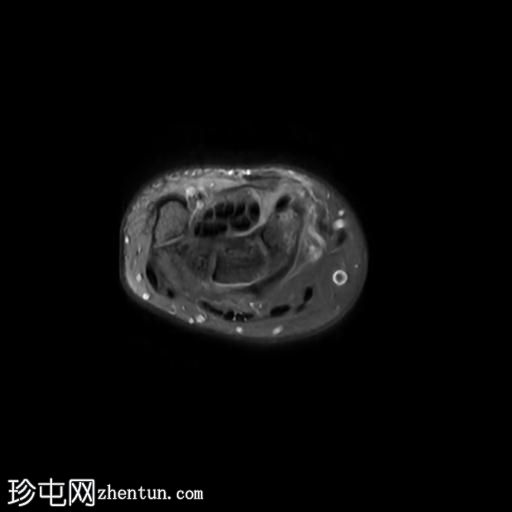

桡侧腕屈肌管综合征

持续性腕掌桡侧疼痛超过5个月。

MRI

轴位

T1加权像

桡侧腕屈肌腱鞘内可见液体信号,提示腱鞘炎

手部桡侧腕屈肌腱远端扁平,邻近的大多角骨嵴和舟骨结节可见反应性骨髓水肿

MRI结果提示存在桡侧腕屈肌腱病变,以及大多角骨和舟骨结节骨髓水肿。桡侧腕屈肌(FCR)肌腱病通常表现为腕关节掌侧(靠近桡侧)疼痛。这种情况通常是由于长期过度使用造成的,尤其是在肌腱与粗糙表面接触的部位。